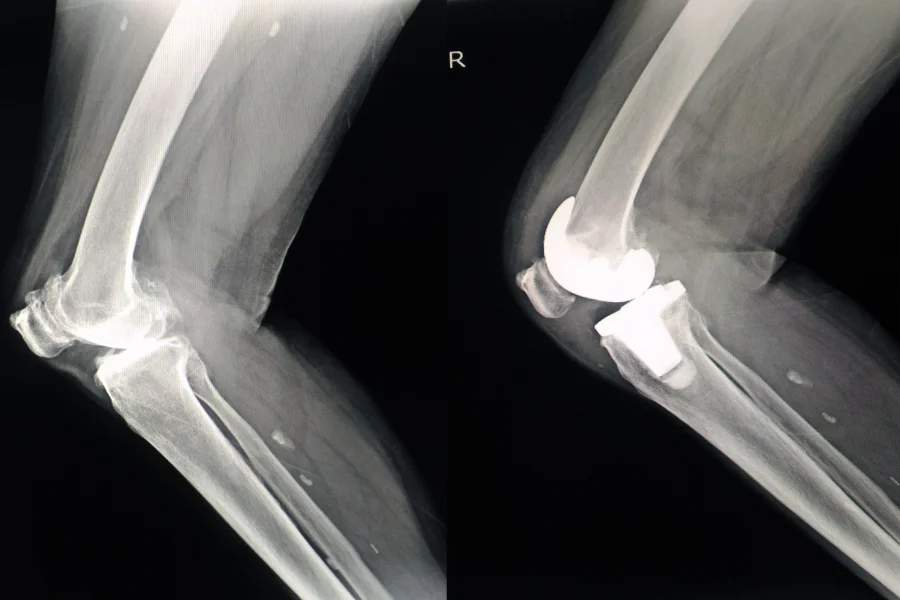

Boy uzatma ameliyatı, bacak kemiklerinin kontrollü olarak uzatılması amacıyla uygulanan cerrahi bir işlemdir. Tıbbi adıyla “distraksiyon osteogenezi” olarak bilinen bu yöntemde, kemik cerrahi olarak kesilir ve özel bir cihaz yardımıyla yavaş yavaş birbirinden uzaklaştırılır. Bu süreçte yeni kemik dokusu oluşur ve kemik uzunluğu artar. Boy uzatma işlemi, hem estetik kaygılarla hem de tıbbi zorunluluklarla uygulanabilir ve genellikle uyluk (femur) ya da kaval kemiği (tibia) üzerine yapılır.

İçten Sabitlemeli Sistemler (Motorlu Çivi - Precice)

Kemiğin içine yerleştirilen ve dışarıdan manyetik kontrolle uzatılan çivilerle uygulanır. Daha az ağrılı, daha konforlu ve estetik açıdan avantajlıdır.